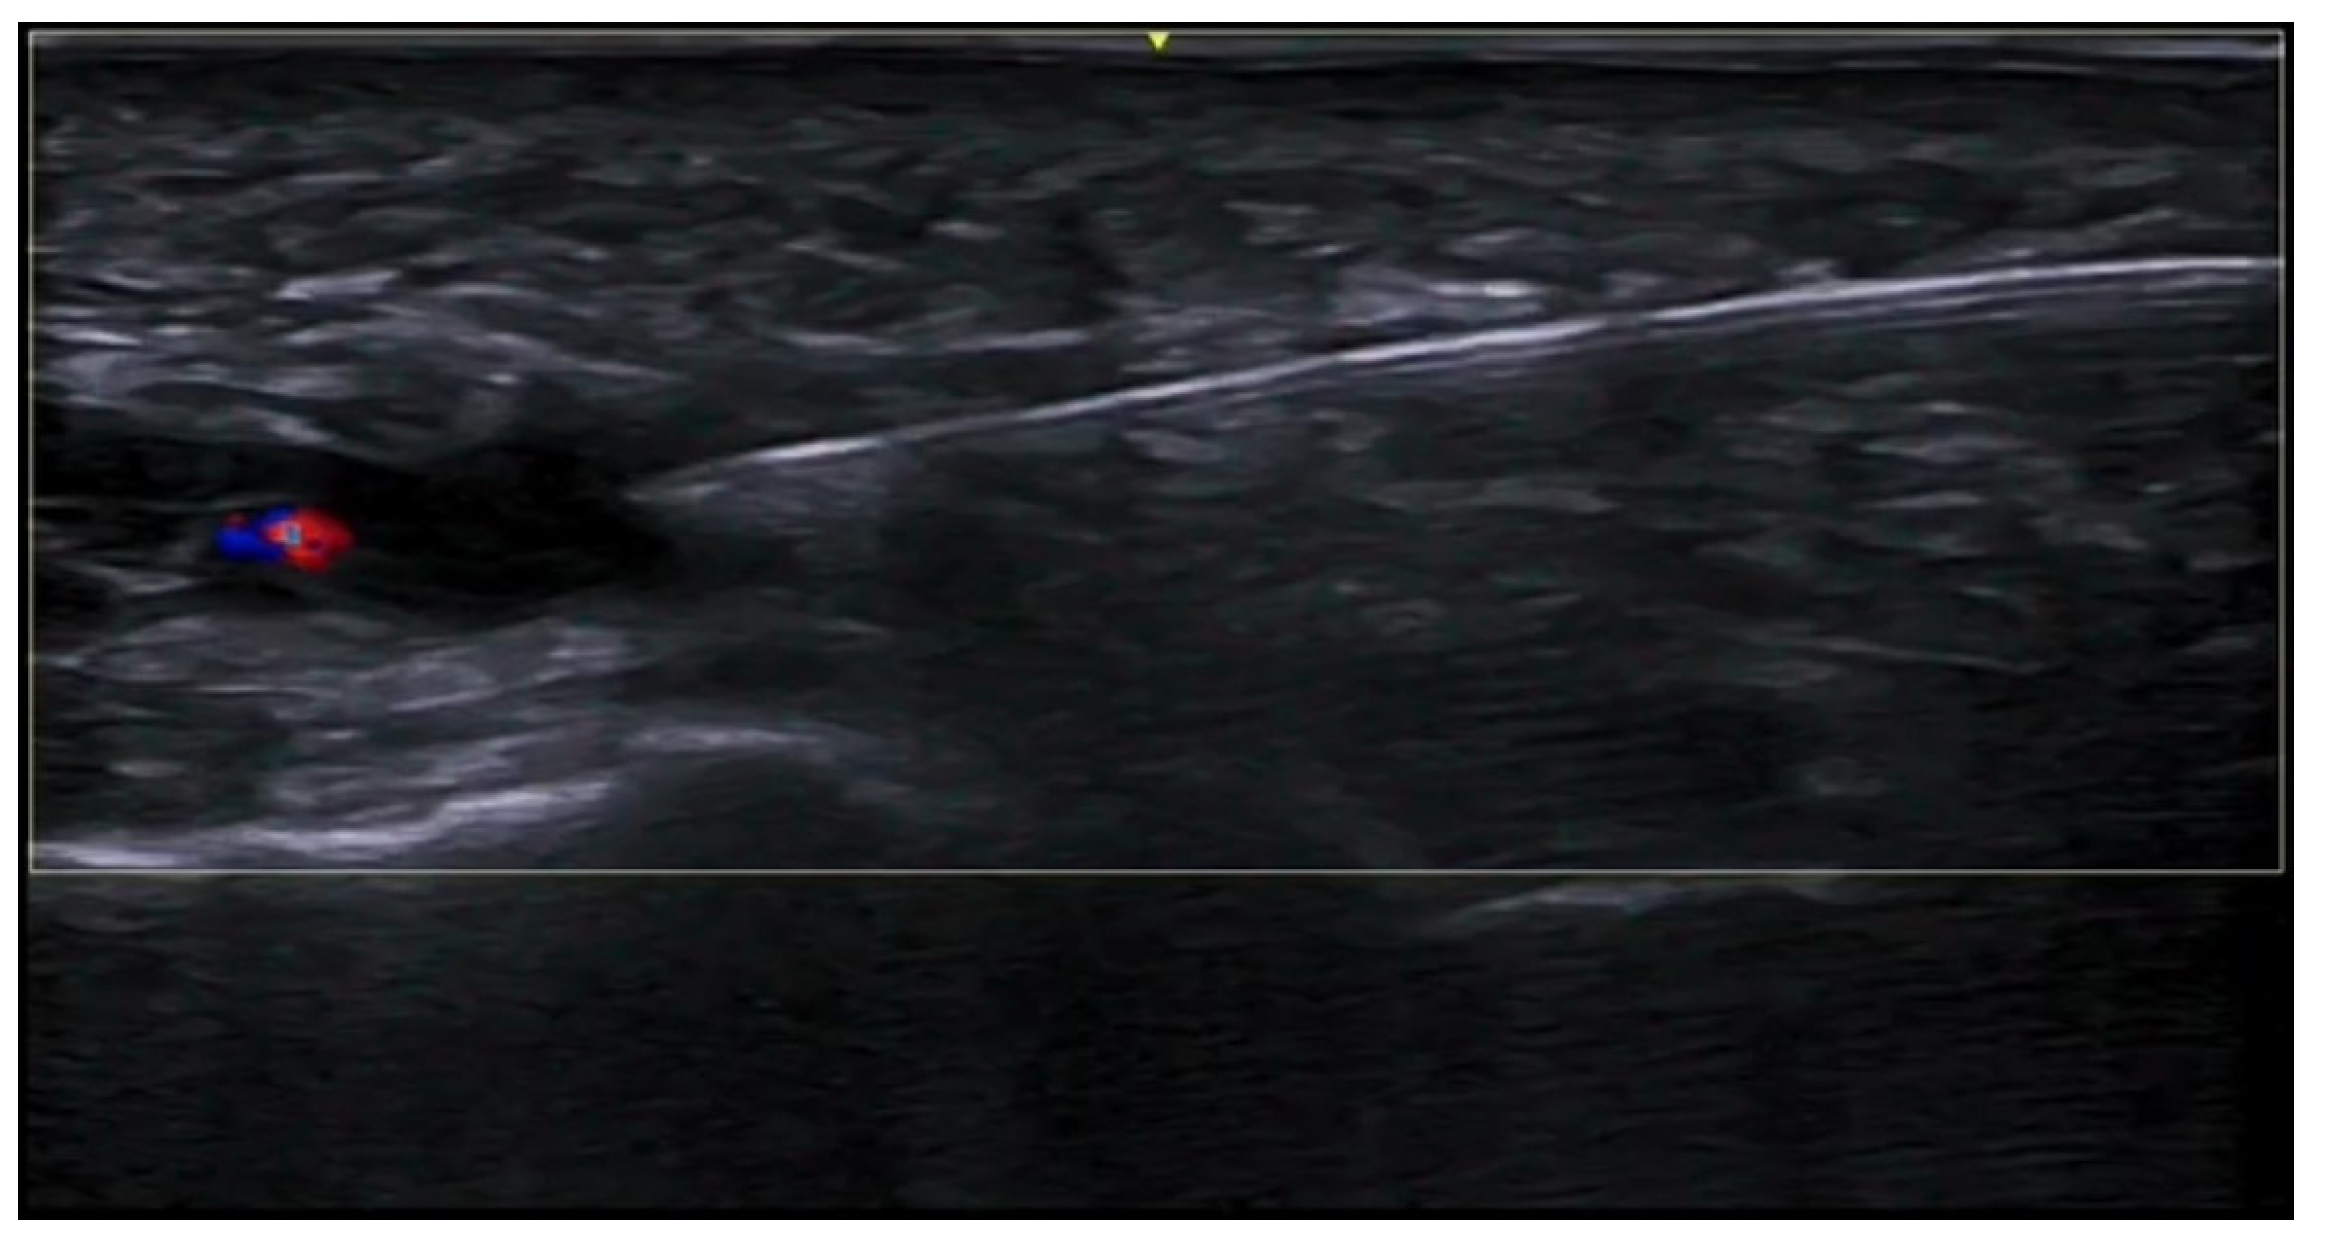

- Di Battista, M.; Vitali, S.; Barsotti, S.; Granieri, G.; Aringhieri, G.; Morganti, R.; Dini, V.; Della Rossa, A.; Romanelli, M.; Neri, E.; et al. Ultra-high frequency ultrasound for digital arteries: Improving the characterization of vasculopathy in systemic sclerosis. Semin. Arthritis Rheum. 2022, 57, 152105. [Google Scholar] [CrossRef] [PubMed]